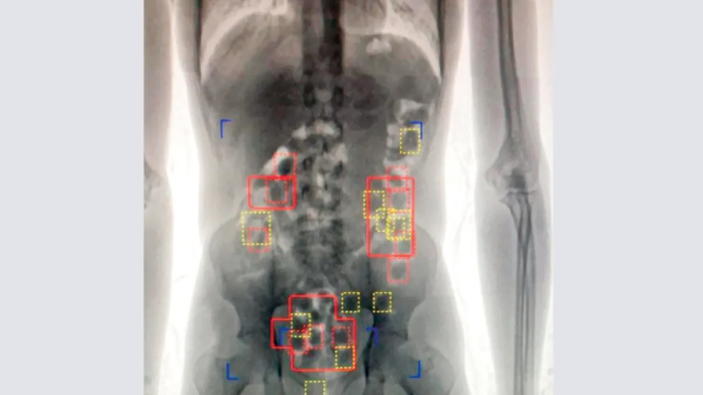

وتعود تفاصيل الواقعة عندما حضر المتهم إلى مملكة البحرين عبر مطار البحرين الدولي قادمًا من بلده الآسيوي وعند مروره بالمنطقة الجمركية اشتبه فيه الشاهد الاول وعليه قام بتفتيشه ولم يعثر على شيء وبسؤاله عن حيازته لأية ممنوعات أنكر إلا أن ملامحه كان يبدو عليها الارتكاب، حيث أمر ضابط الجمارك بتحويله إلى غرفة جهاز الأشعة وبالعرض عليه لوحظ وجود أشكال دائرية بداخل أحشائه مشتبه في أنها كبسولات مخدرة فتم تحويله إلى مكتب إدارة مكافحة المخدرات .

وبسؤال المتهم أقر بابتلاع كبسولات تحتوي على المواد المخدرة قاصدًا تهريبها الى مملكة البحرين وعليه تم تحويله الى مستشفى وزارة الداخلية وقام بإنزال عدد من الكبسولات على دفعات في اثناء مراقبة عملية إنزال الكبسولات حتى بلغ مجموع الكبسولات 84 كبسولة .